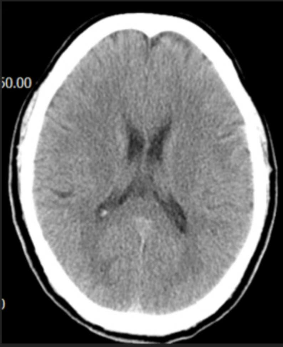

急診心電圖:未見(jiàn)明顯異常。頭顱CT:如圖。

(3)頭顱CT未見(jiàn)明顯異常,可排除腦出血。(0.5分)